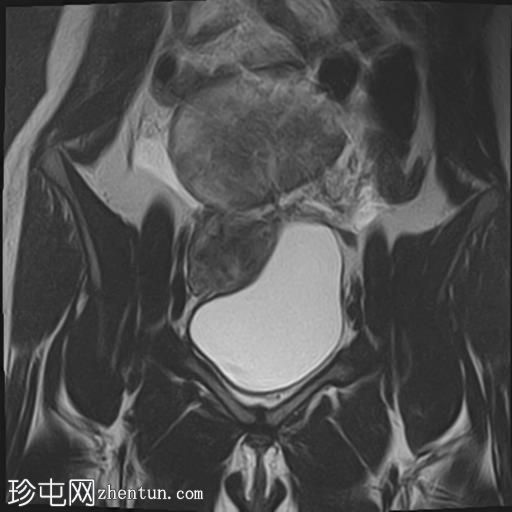

轴位T1加权像

增强脂肪抑制像

其中一个位于子宫上方,T2加权像呈中等信号,中心区域呈高信号,增强T1脂肪抑制像未见强化。右侧卵巢增大,增厚的血管蒂扭曲,未见强化,轴位和矢状位T2加权像均显示清晰。

另一个位于子宫后窝,T2加权像呈中等信号,增强扫描显示明显强化。